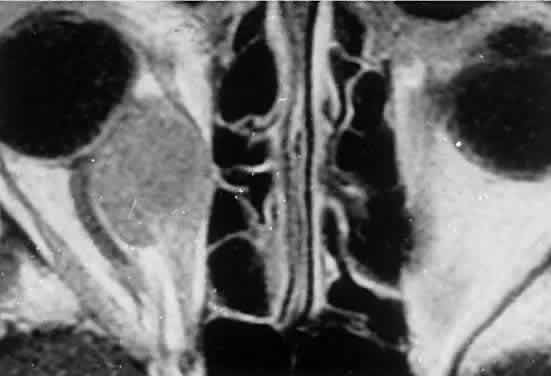

Within the orbit, rhabdomyosarcoma occurs most often, but not exclusively, in the superior nasal quadrant, with downward and outward displacement of the globe. CT scans show the topography of the orbital mass (Fig. 1A), as well as the possible extension into adjacent bone, paranasal sinuses, or the intracranial cavity. The circumscription that may be noted on CT is relative, because the lesion is not encapsulated and microscopically infiltrates normal tissue. Echography shows internal echoes of low-to-medium amplitude. Because the cellular tumor absorbs acoustic energy, the amplitude of the spikes falls off somewhat through the lesion (see Fig. 1B and C). MRI can help define the tumor's relationship to extraocular muscles (Fig. 2).

Fig. 1. A. Proptosis and downward, outward globe displacement developed over 2 days in a 3-year-old girl. A homogeneous mass fills the superomedial orbit. B. Contact B-scanning shows a relatively well-circumscribed mass with uniform internal echoes. C. Contact A-scanning shows the internal reflectivity to be of low to medium amplitude, consistent with a sarcomatous lesion. Biopsy results confirmed the diagnosis of rhabdomyosarcoma.

Fig. 2. MRI shows an intraconal tumor of lower intensity than the medial rectus muscle. The proximal muscle is splayed rather than compressed, suggesting that the lesion originated within the medial rectus. The diagnosis was alveolar rhabdomyosarcoma.